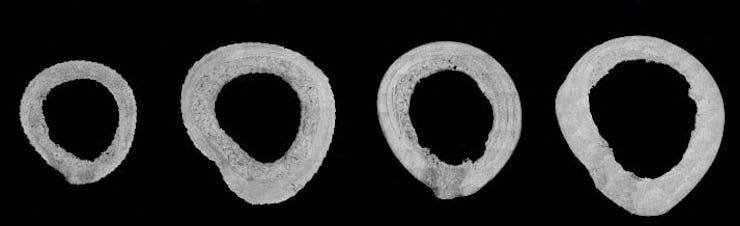

What’s new — Researchers analyzed a one-centimeter sample of the thigh bones from seven macaques that died of natural causes. Three came from males and four from females. Two of the females had given birth in their lifetime, and two had not.

Microscope images of the cross-section of the seven femora (thigh bones) included in this study, identified by age and sex.